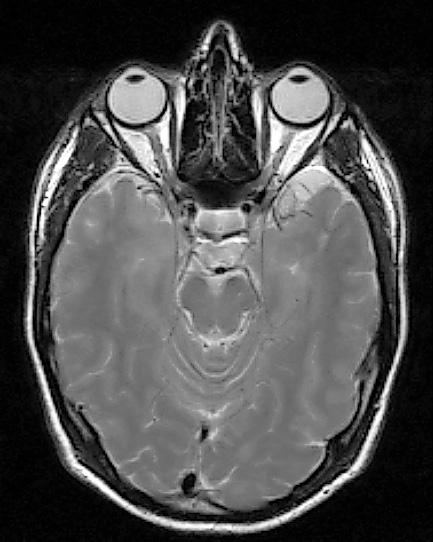

venstre øye høyre øye chiasma opticum n. opticus tractus opticus corpus geniculatum laterale area striata radiatio optica Figur 2.18 Synsbanen. Figur 2.19 Computertomografi (Ct) av øyehulene med synsnervene.

Figur 2.20A magnetisk resonanstomografi (mR) av øyehulene og hjernen. Figur 2.20B mR viser synsnervene, chiasma opticum og overgang til tractus opticus.